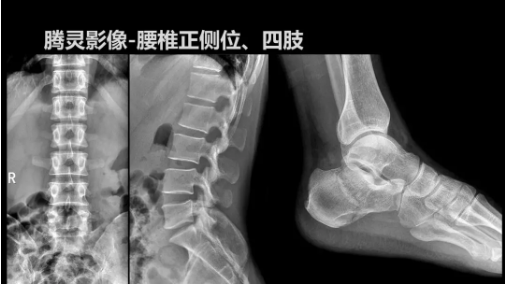

“騰靈”是安健科技的第四代動(dòng)態(tài)DR產(chǎn)品,可實(shí)現(xiàn)全科室應(yīng)用。如各類常規(guī)的X線檢查、消化道檢查、骨科檢查、婦科、兒科檢查等。此外,安健科技為“騰靈”在真正意義上實(shí)現(xiàn)多科室、多功能診斷進(jìn)行了多項(xiàng)針對(duì)性設(shè)計(jì)。

其中包括SID范圍可調(diào)節(jié)能夠滿足多種類攝影要求、球管角度可調(diào)節(jié)能夠滿足不同投照部位的需求、超低床體設(shè)計(jì)方便患者上、下床、360°可旋轉(zhuǎn)腳踏板降低擺位難度、可移除式濾線柵能夠滿足兒科等特定場(chǎng)景的計(jì)量要求、可升降操控臺(tái)方便醫(yī)生床旁操作等,并配置了全身拼接功能,最大程度上適配動(dòng)態(tài)DR產(chǎn)品的特點(diǎn)。

相較前代產(chǎn)品,“騰靈”在圖像質(zhì)量方面得到了全面升級(jí),“騰靈”采用17*17非晶硅平板探測(cè)器設(shè)計(jì),采集矩陣達(dá)3072*3072,動(dòng)態(tài)范圍達(dá)16bit,為成像提供超大視野的同時(shí)保證成像質(zhì)量,此外,該款機(jī)型可根據(jù)醫(yī)療機(jī)構(gòu)的差異化需求而選配不同的動(dòng)態(tài)平板探測(cè)器,以此來適應(yīng)不同階層用戶所需。